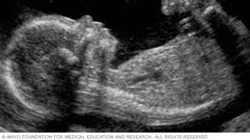

The image below shows a fetus's profile at 11 weeks of pregnancy, which is nine weeks after conception. At this stage, the head makes up about half of a fetus's length.